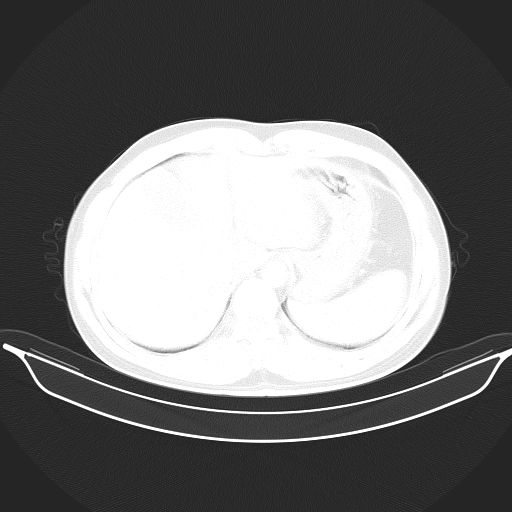

考虑:1、过各敏性肺炎可能性大,建议定期复查。

2、轻度脂肪肝。